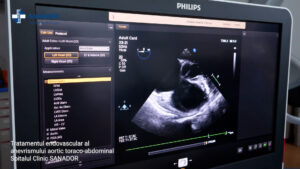

TRATAMENTUL ENDOVASCULAR AL ANEVRISMULUI TORACO-ABDOMINAL

O nouă premieră națională în tratamentul complex minim invaziv al bolilor cardiovasculare a fost realizată la Spitalul Clinic SANADOR de echipa medicală condusă de Prof. Dr. Victor Costache. Este vorba de un pacient de 48 de ani, diagnosticat cu anevrism aortic toraco-abdominal, tratat endovascular. În rezolvarea cazului a fost utilizată o proteză vasculară personalizată, realizată de Terumo Aortic.

Tratamentul endovascular, realizat în premieră pentru România la Spitalul Clinic SANADOR, este disponibil în doar câteva centre de excelență din Europa.